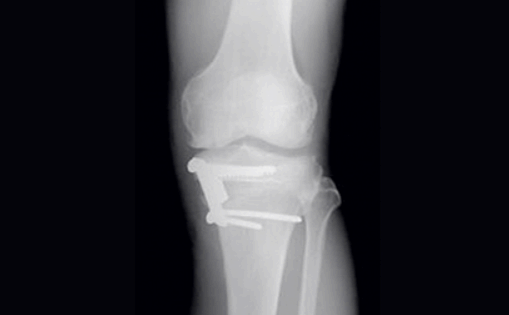

주사요법으로도 치료가 어려운 경우에는 관절내시경 수술을 통해 연골을 재생시키는 방법이 있습니다. 이를 연골 입자 이식술이라고 하는데요. 원래의 연골 중 일부를 떼어내서 이를 손상부에 주입함으로써 연골을 재생하는 방법입니다.

이 방법은 기존 방법과는 달리 재생되는 연골이 원래의 연골 성질과 내구성이 비슷한 연골로 재생이 되므로 이후에 퇴행성 관절염을 예방하는데 효과가 있습니다. 연골이 스스로 재생되지 않기 때문에 인위적인 방법으로 재생을 해주어야 합니다. 이 방법 역시 완전한 재생은 어렵기 때문에 평소 무릎을 사용할 때 주의하시는 것이 중요합니다.

이 밖에도 뼈와 연골 일부를 제거하고 인공관절을 삽입하는 수술로 통증이 심해 일상생활이 불편하신 분들에게 적당한 인공관절치환술이 있고, 연골판 양쪽을 십자 형태로 봉합하는 십자봉합술이 있습니다. 이는 정상 모양과 유사하도록 안착시켜 주는 방식으로 강도를 높여주고 있습니다.